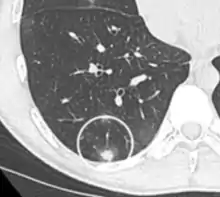

Round well-delineated solid lung nodule with smooth border.[9]

Lobulated nodule.[9]

Spiculated lung nodule.[9]

A "notch sign".[9]

A triangular perifissural node can be diagnosed as a benign lymph node.[9]